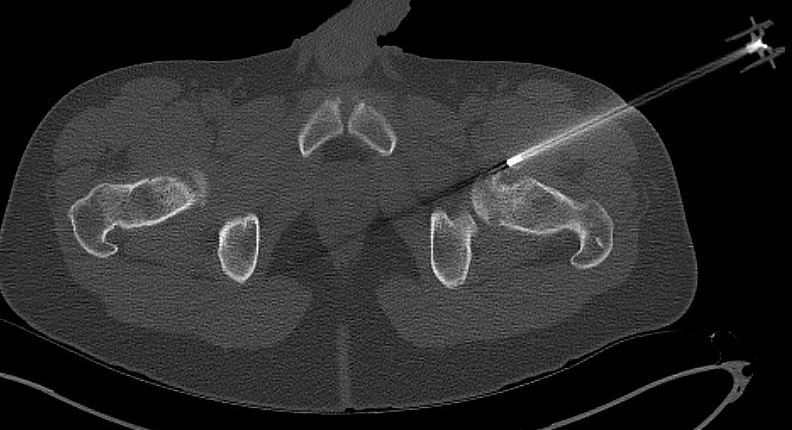

CT

CT periosteal chondromaCT periosteal chondroma